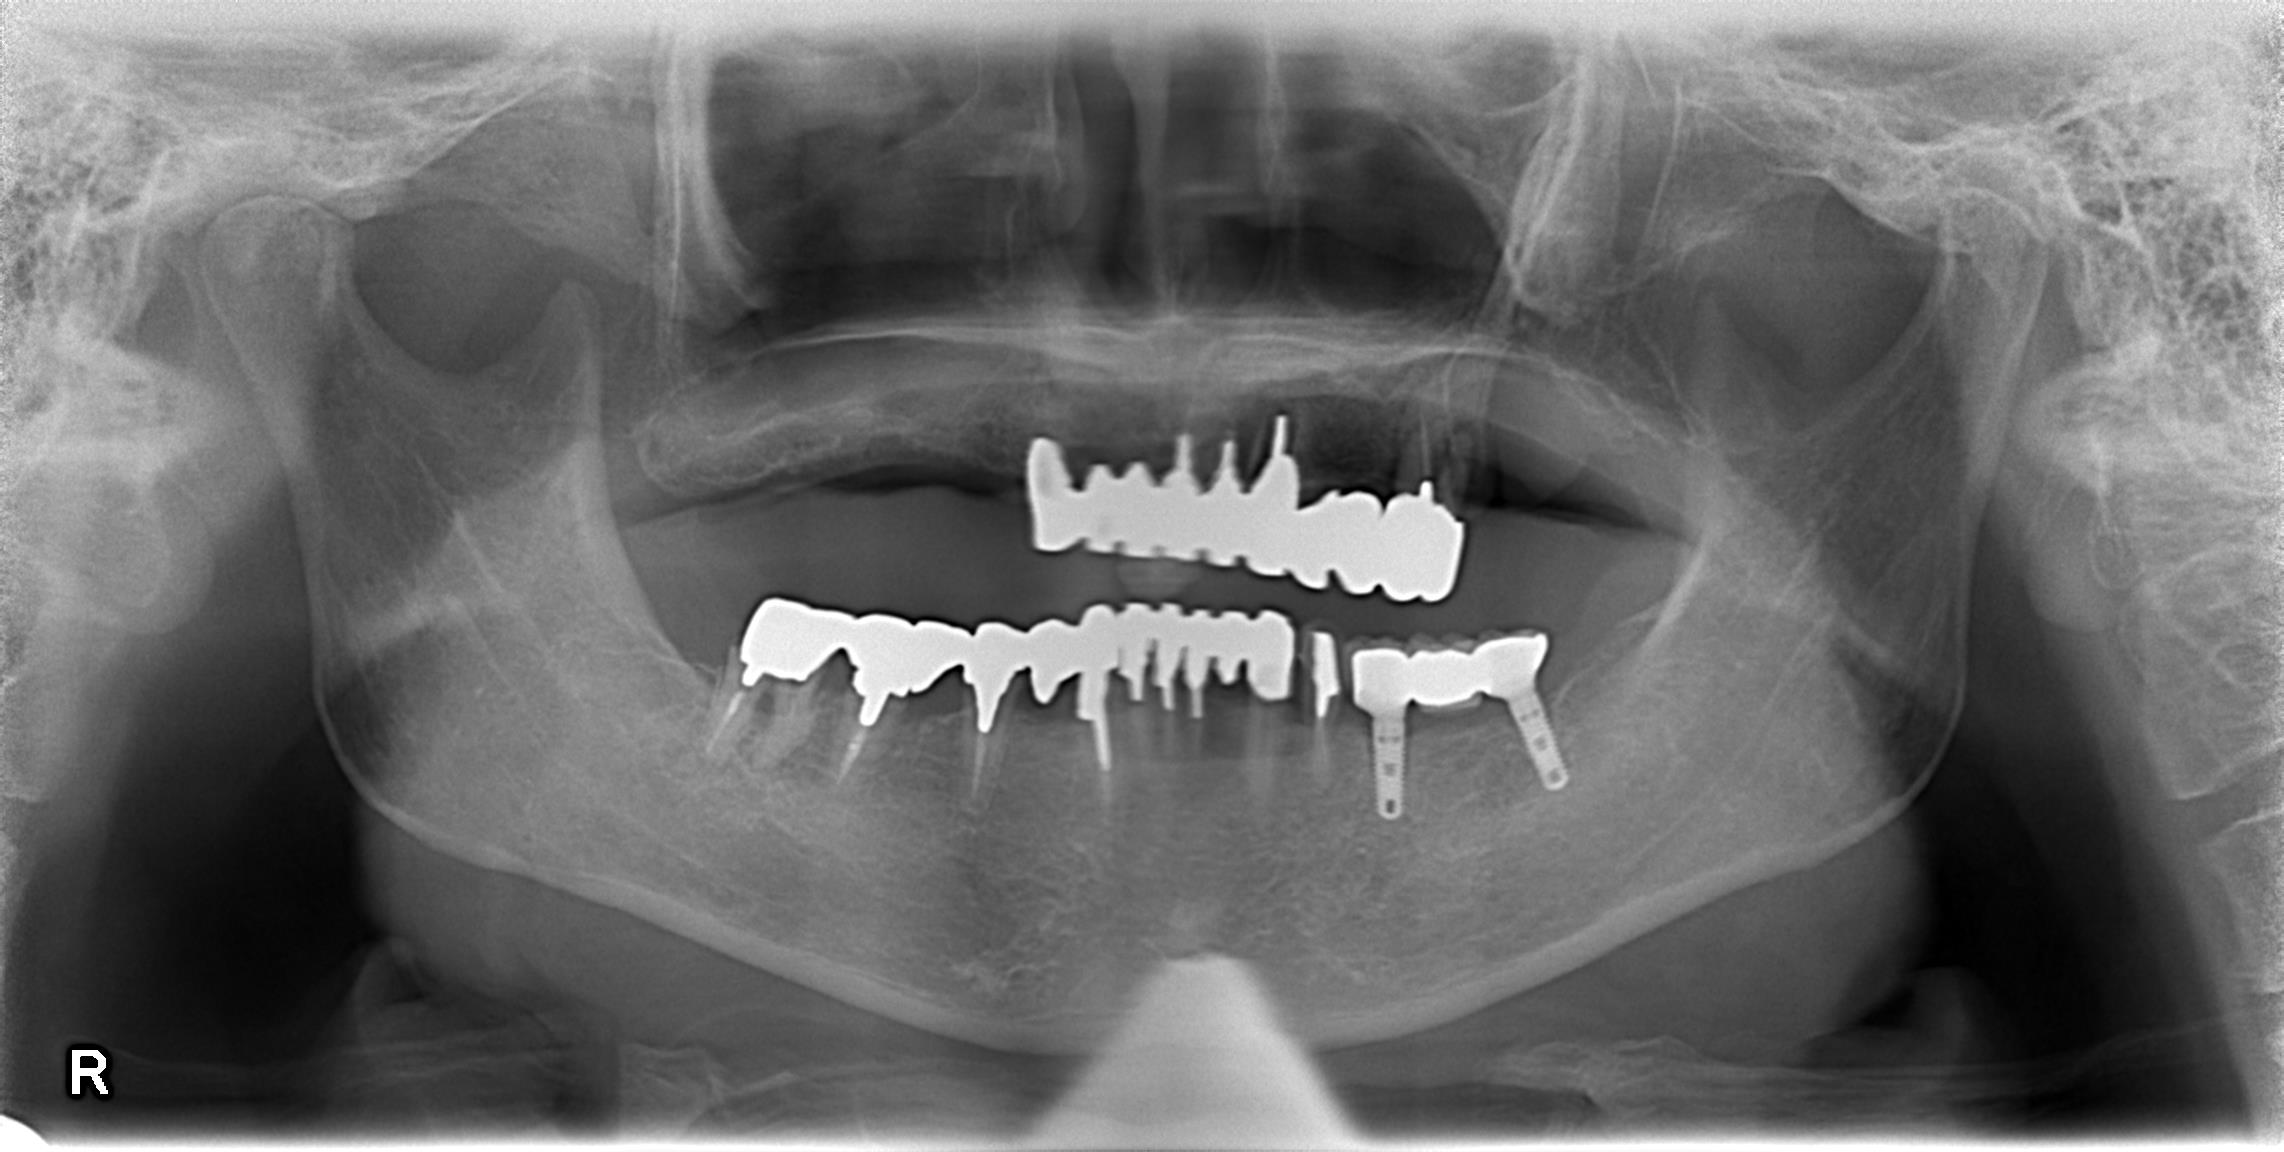

左の奥歯はインプラント治療をしたが、他の歯をみて欲しい、ということで来院されました。

左下はインプラント治療が施されていましたが、他の歯は保険適応の被せ物、ブリッジ治療が行われており、全てが虫歯になっていました。

60代後半の方で、もう1回あの治療を行うのはしんどい、歯で困らないようにしてほしい、ということで相談した結果、全ての残っている歯を抜歯、インプラント治療と総義歯の治療を併用することになりました。

現在仮歯で噛み合わせの調整を行なっているところです。

上記の写真をご覧になっていただければ、なんとなく綺麗だと思っていただけると思います、仮歯でこの状態です。

残っている歯を全部除去することで、歯科医師・歯科技工士は自由に歯を配置することができます。

ひいてはそれはバランスのいい歯列、歯並びを構築することにつながります。